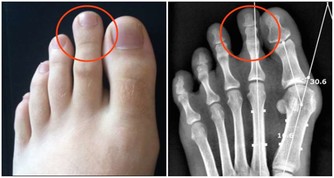

4.指甲異色症(Terry’s nails)

指甲近端約80%產生變白的現象。

這種情況通常歸因於老化,但它也是肝硬化、心臟衰竭或糖尿病的指標。